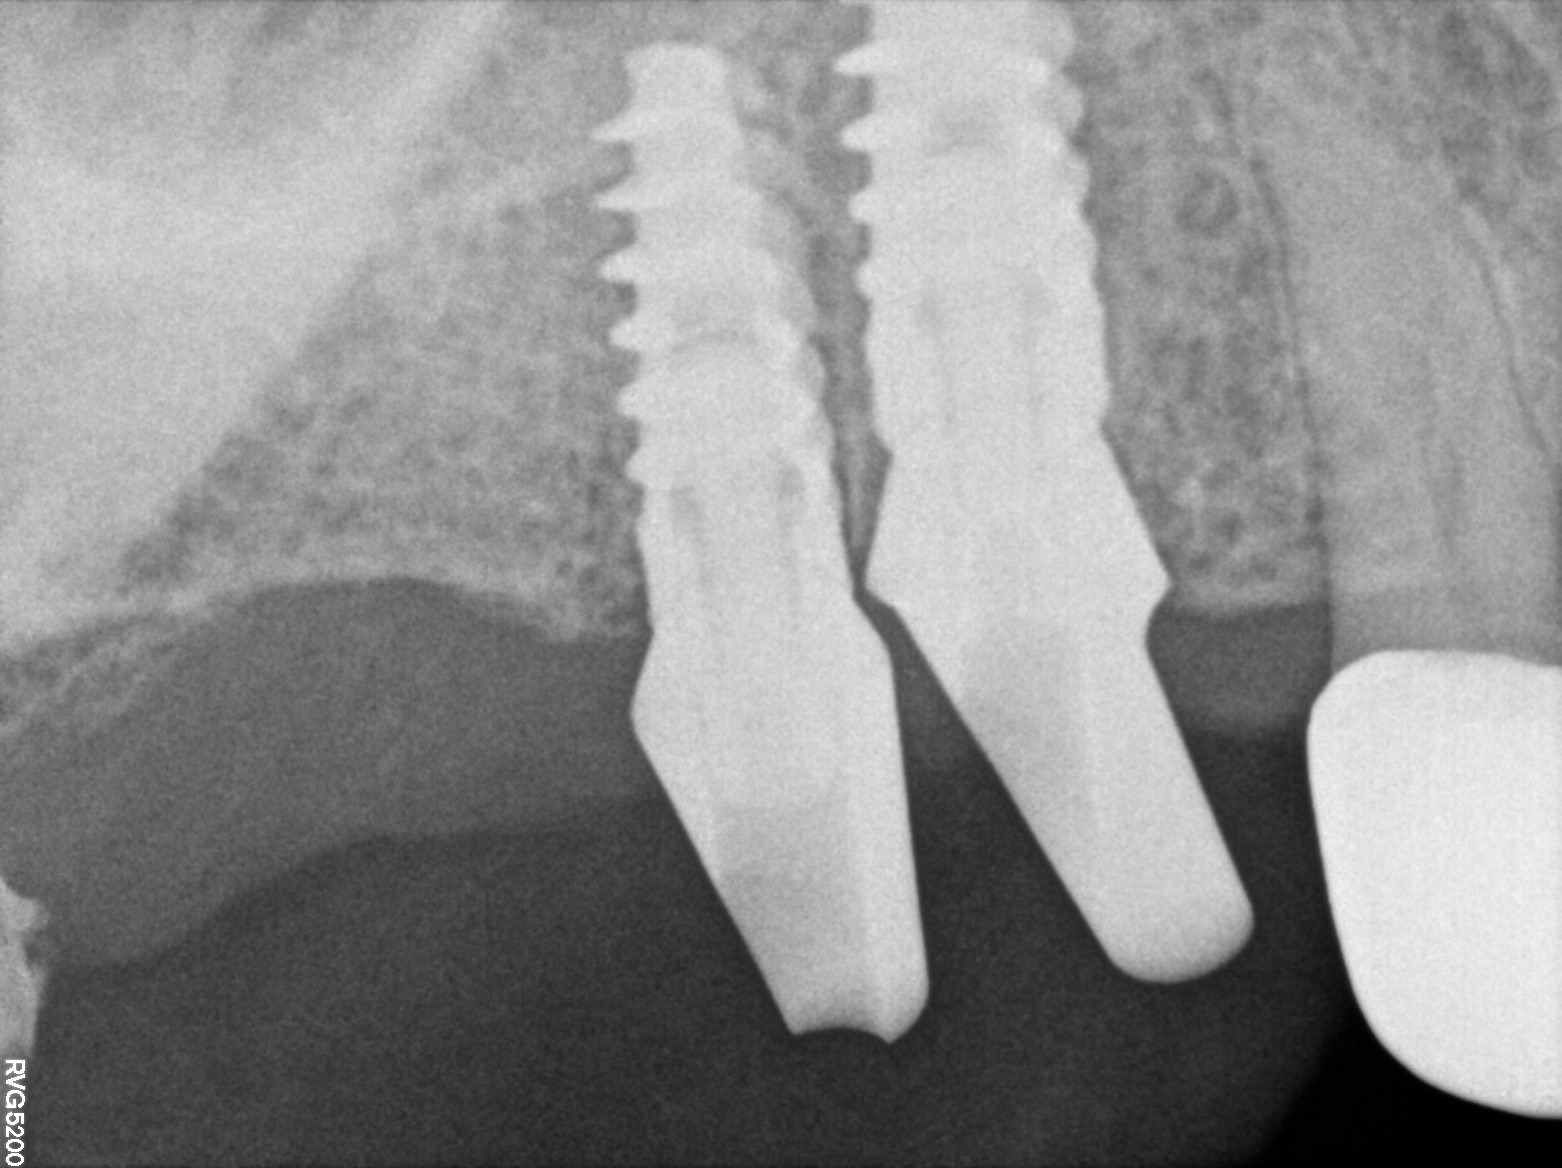

Dental Radiographs FHIR: DocumentReference · LOINC 24641-7

R71.jpg

24641-7